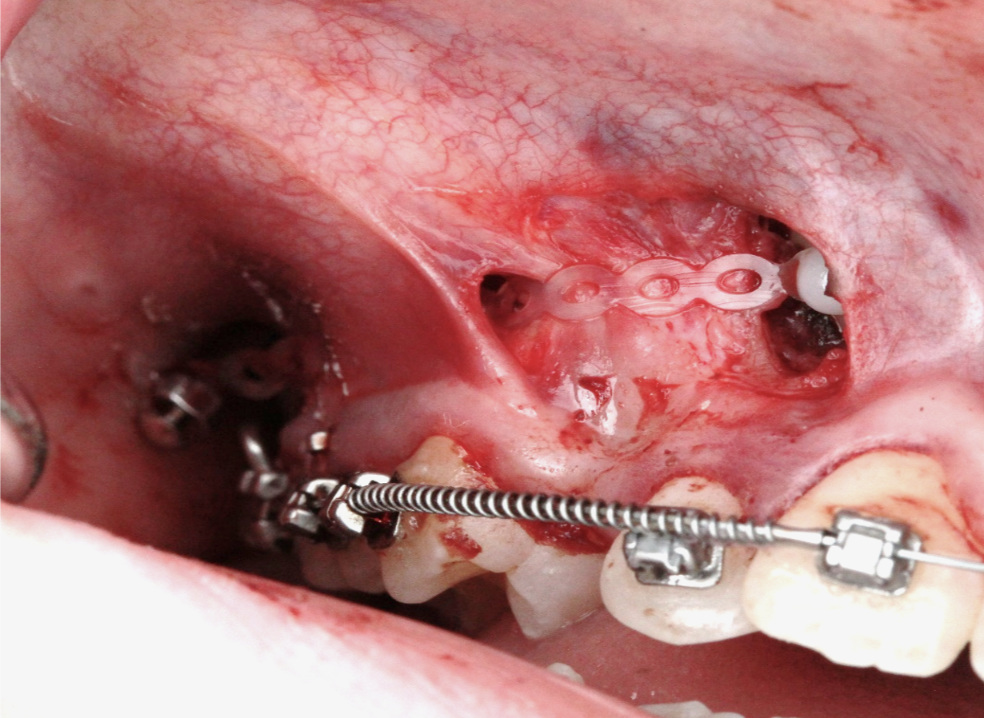

Мир мягких тканей в хирургической стоматологии

На курсе вы научитесь уменьшать негативные последствия хирургических вмешательств в полости рта и снижать риски осложнений.

Обучить стоматологов-хирургов методам минимизации негативных последствий хирургических вмешательств и снижения рисков осложнений, а также освоению современных методов работы, разработанных на основе зарубежных передовых методик мягкотканной пластики.

Программа курса

День 1. Теоретическая часть

• Ведение лунки удаленного зуба. Работа с оро-антральным сообщением. Менеджмент десневого края при различных типах дефекта вестибулярной костной стенки. Классификация мичиганского университета.

• Мультимодальное обезболивание при различных хирургических манипуляциях в полости рта.

• Взаимодействие лекарственных препаратов.

• Варианты действий при одномоментной имплантации в лунку удаленного фронтального зуба и низком торке: "шайба" по Ноймайеру, VIP-CT, Essex.

• Аугментация твердых и/или мягких тканей при одномоментной имплантации? Фронтальная группа зубов или жевательная. Есть ли разница?

• Моделирование провизорных конструкций при мягко-тканевых пластиках.

• Дизайн разреза в полости рта. Критерии принятия решения.

• Выбор рабочих вариантов швов из многообразия.

• Биотип тканей и пассивное закрытие раны. PASS-принцип.

• Мобилизация небного лоскута.

• Критические параметры десны для долгосрочного функционирования дентальных имплантатов.

• Оптимальное время для подсадки десны при дентальной имплантации.

• ССТ, СДТ, Показания.

• Осложнения при подсадке десневых трансплантатов в эстетически значимой зоне.

• Открытое и закрытое заживление аутогенных трансплантатов десны.

• Индивидуальный формирователь десны при одномоментной имплантации. Настолько ли он хорош?

• Ограничения аутогенных мягко-тканных трансплантатов.

• Роль и место биоматериалов для аугментации тканей.

День 2. Практическая часть на биофантомах

• Консервация лунки с помощью десневых трансплантатов (свободный десневой, VIP-CT).

• Ролл-техника для компенсации дефицита объема тканей в эстетической зоне.

• Упрощенный способ забора мягких тканей с бугра верхней челюсти.

• Мобилизация щечного лоскута различными способами.

• Небный скользящий лоскут.

• Рабочие швы для повседневной практики.

Вы научитесь

• Вести лунку удаленного зуба и управлять оро-антральным сообщением.

• Применять мультимодальное обезболивание при различных хирургических манипуляциях в полости рта.

• Выполнять одномоментную имплантацию с аугментацией твердых и мягких тканей, включая использование техник "шайба" по Ноймайеру, VIP-CT и Essex.

• Правильно выбирать и применять различные виды швов для достижения пассивного закрытия раны.

• Мобилизовать небный лоскут и компенсировать дефицит объема тканей в эстетической зоне с использованием ролл-техники.

• Извлекать мягкие ткани с бугра верхней челюсти и мобилизовать щечный лоскут различными способами.

• Выбирать тип швов подходящий для каждой клинической ситуации.

Фотогалерея